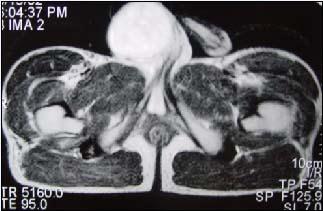

29岁男性患者,右侧睾丸肿痛5个多月,行MRI检查,如图所示,T1加权见右侧阴囊内见球形肿块,呈中等信号,其内信号不均,T2加权肿块为高信号,最可能的结果...

问题 29岁男性患者,右侧睾丸肿痛5个多月,行MRI检查,如图所示,T1加权见右侧阴囊内见球形肿块,呈中等信号,其内信号不均,T2加权肿块为高信号,最可能的结果是()

选项 A.精原细胞瘤 B.睾丸结核 C.畸胎瘤 D.皮样囊肿 E.畸胎癌

答案 A